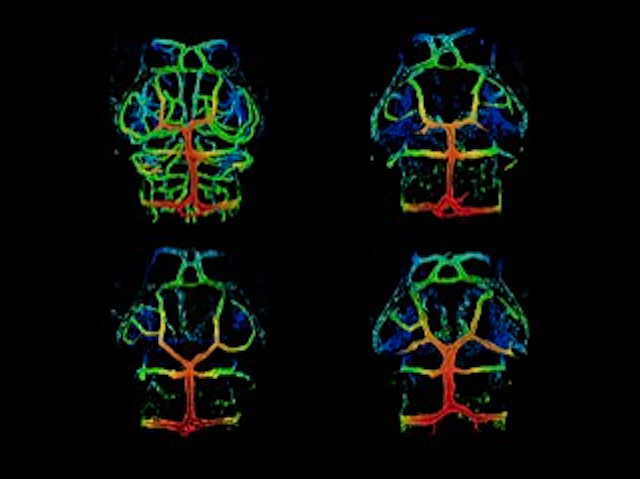

Brain Leaks

Every heartbeat sends around a quarter of your blood volume to your brain, mainly via the blood-brain barrier – a network of blood vessels that don’t allow large molecules to leak out. However, certain parts of your brain have leakier blood vessels called fenestrated capillaries that do allow large molecules through. Researchers investigate how these vessels form using fluorescence microscopy of zebrafish brains with fluorescently-tagged blood vessels (pictured). They focused on signalling pathways already implicated in blood vessel development, Wnt and VEGF. Zebrafish lacking certain Wnt signalling molecules (bottom, top right) had severely disrupted blood-brain barrier vessels compared with normal brains (top left) while fenestrated capillaries were unaffected. Conversely, in zebrafish lacking different combinations of VEGF members, fenestrated blood vessels were severely disrupted. Notably, VEGFC and/or VEGFD were vital for fenestration and in certain regions, fenestration involved VEGFC interacting with VEGFA. A VEGF cocktail is, therefore, essential for developing fenestrated capillaries.